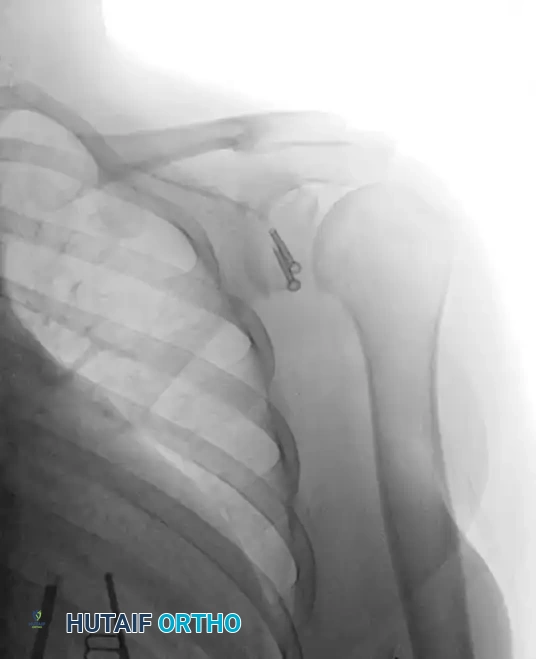

Image

Postoperative Anteroposterior (AP) radiograph demonstrating parallel screw fixation of the Latarjet graft.